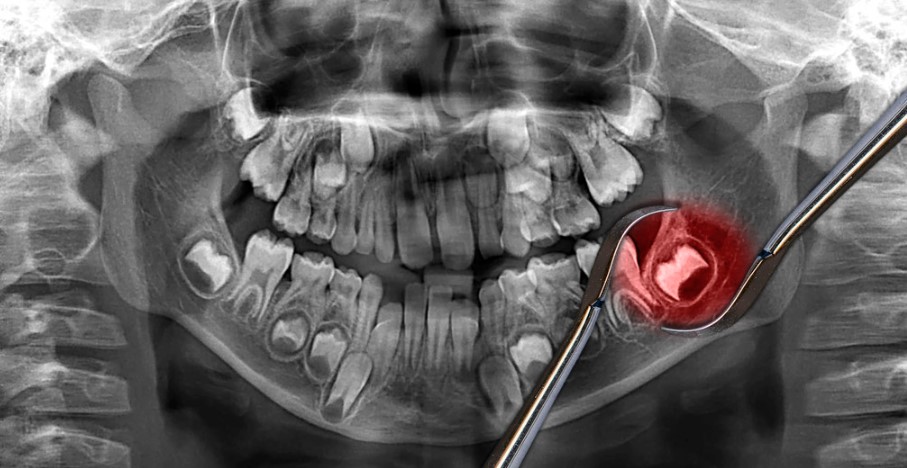

The process of wisdom tooth removal begins with a consultation and examination by a dental professional in Melbourne. During this initial visit, the dentist will evaluate the position and condition of the wisdom teeth using X-rays and visual examination. They will discuss the treatment options and address any concerns or questions the patient may have.

Impacted wisdom teeth occur when there is not enough space in the mouth for them to fully emerge or grow in the correct position. Impaction can be partial, where the tooth is only partially erupted, or complete, where the tooth is trapped within the jawbone. Impacted wisdom teeth can cause pain, swelling, and infection.

Wisdom teeth are more difficult to clean due to their location at the back of the mouth. As a result, they are prone to developing infections and gum disease. The presence of partially erupted wisdom teeth creates pockets of space where food particles and bacteria can accumulate, leading to inflammation, infection, and potential damage to surrounding teeth and tissues.